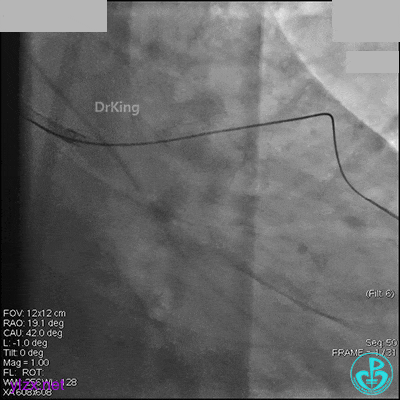

AL 1.0指引导管到位,简单短时尝试导丝不能顺利通过前降支或回旋支病变。改变策略处理右冠脉病变,计划植入2枚支架。AL指引导管到位,Sion blue导丝到达右冠脉远端。导丝通过后1.5mm及2.5mm球囊14~16atm充分扩张中段病变。

右冠脉中段充分扩张后欲植入3.5×38mm支架时,支架难以通过中远段扭曲处,且指引导管、导丝弹出飞扬。反复尝试导丝重新到达右冠脉远端时通过不顺利,局部造影剂滞留,远端血流接近3级。